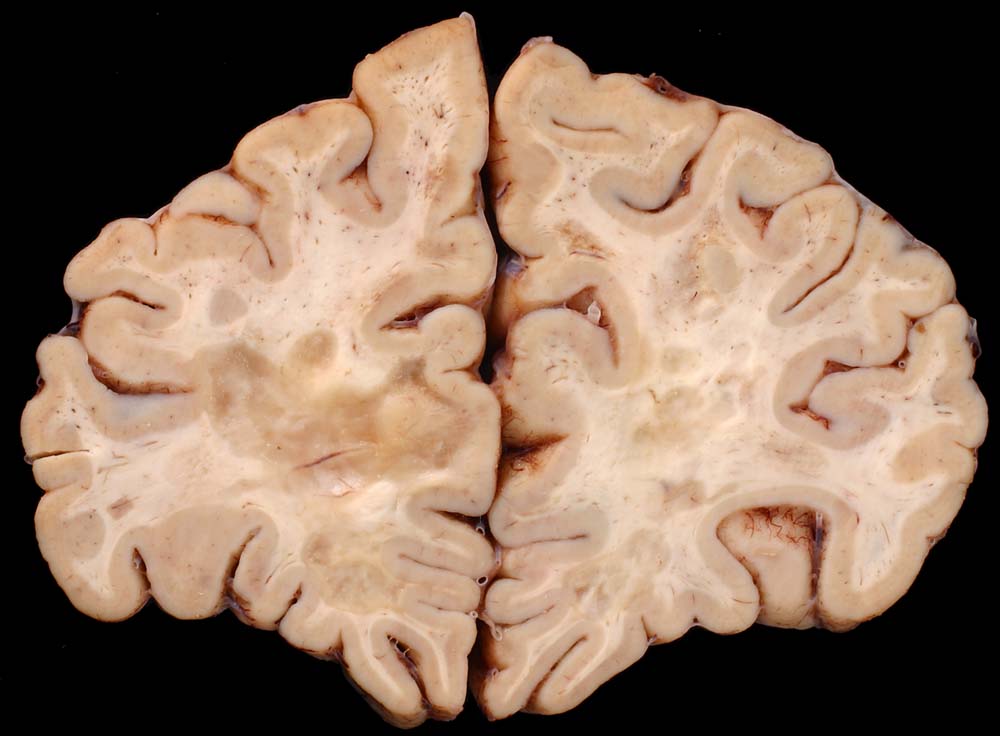

PathoPic – image database / PathoPic ID 8683 - Entmarkungsherde bei Multipler Sklerose

Entmarkungsherde bei Multipler Sklerose

Fleckförmige Grauverfärbung des Marklagers ( Entmarkungsareale).

Chronische und aktive Entmarkungsareale in der weissen Substanz (beidseits, periventrikulär betont).

Diagnose einer multiplen Sklerose vor 12 Jahren. Paraparese der Beine. Neurogene Blasenentleerungsstörung. Seit einem Jahr deutliche neurologische Verschlechterung.